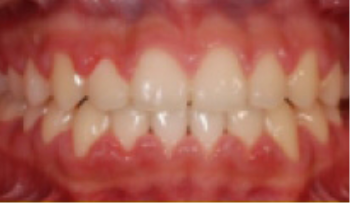

• 과개교합 아랫니와 윗니가 깊게 물려 아래 앞니가 잘 안 보임.

Before

After